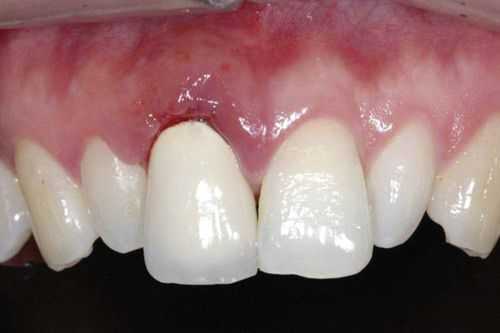

- Удаление пульпы 33 и 36 зубов с трёхмерным пломбированием корневых каналов с последующим изготовлением и фиксацией мостовидного протеза на основе диоксида циркония с опорой на 33 и 36 зубы.

После удаления мостовидного протеза с зубов 33 и 36, покрытого нитрид титаном, пациент отметил значительное уменьшение дискомфорта, жжения, кислого вкуса в ротовой полости. Через две недели после установки мостовидного протеза на основе диоксида циркония чувство жжения и покалывания языка исчезли совсем.

При осмотре пациента через полтора месяца после окончания ортопедического лечения отмечено удовлетворительное состояние полости рта и исчезновение дискомфорта. Через три месяца после протезирования пациент не предъявлял никаких жалоб.